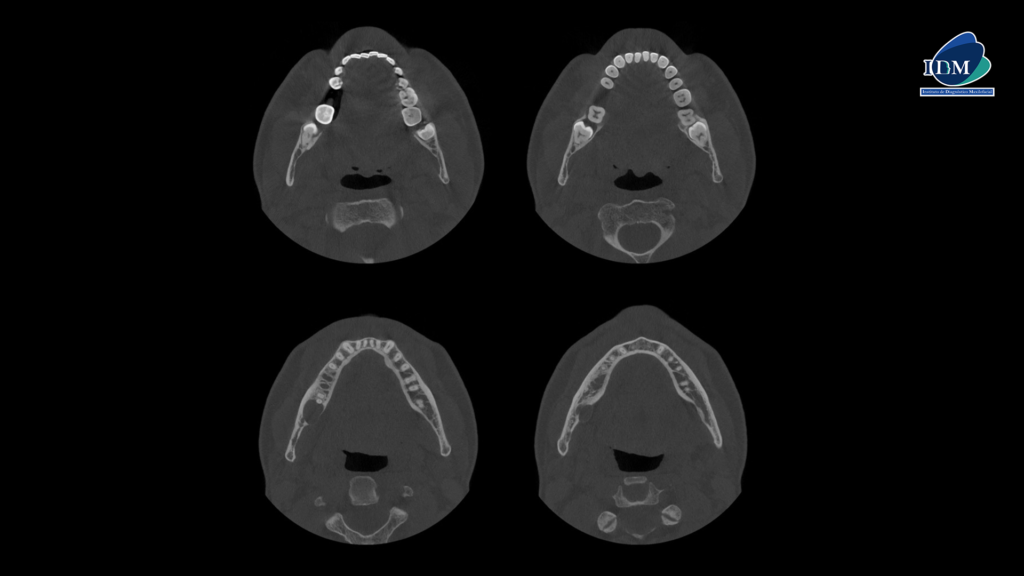

A la evaluación de la tomografía volumétrica (CBCT) en los cortes axiales (Figura 2) y transaxiales (Figura 3), se aprecia imagen isodensa pericoronaria, de limites definidos, bordes parcialmente corticalizados, que se extiende en sentido cefálico caudal desde cima del reborde alveolar hasta a nivel de cortical inferior del conducto dentario inferior, en sentido mesio distal desde distal de pieza 47 hasta tercio cervical radicular de pieza 48, que ocasiona el borramiento parcial de la lámina dura en raíz distal de pieza 47, adelgazamiento y expansión de la tabla ósea lingual, erosión parcial de la cortical de cima del reborde alveolar, borramiento parcial de la cortical del conducto dentario inferior.

CORTES AXIALES